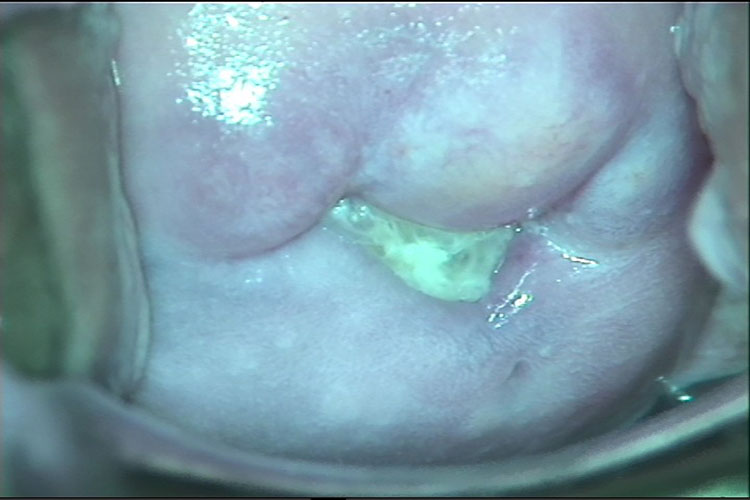

急性型:主要表现为阴道分泌物增多及外阴瘙痒,呈稀薄脓性、黄绿色、泡沫状,有臭味分泌物,可伴有腐败臭味、灼热、疼痛、性交痛等症状。妇科检查时可见阴道黏膜充血、严重者有散在的出血斑点,形成“草莓样”宫颈。后穹窿有多量白带,呈黄绿色、灰黄色或黄白色稀薄脓性分泌物,常呈泡沫状。